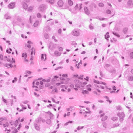

To deal with some of the aforementioned issues, we introduce a new approach for simultaneous H&E stain normalization and augmentation based on the multimarginal Wasserstein barycenter approach. Specifically, the novelty of the paper lies in first introducing the traditional Wasserstein barycenter approach for stain normalization/augmentation (Figure 1), and then introducing the multimarginal version [1, 9] to overcome the limitations of the traditional approach in this context (Figure 2). Note that the traditional Wasserstein barycenter (1 source and 1 reference), although widely employed in computer vision, to the best of our knowledge has never been used for stain normalization/augmentation and the more general multimarginal Wasserstein barycenter (1 source and multiple references) has hardly ever been used in computer vision or medical imaging communities. For more accurate stain normalization, the multimarginal version allows one to incorporate additional distributions by utilizing one or more intermediate reference images (Figure 2). The resultant interpolations span a broad spectrum of stain variations allowing for simultaneous stain normalization and augmentation.

We used MITOS-ATYPIA’14 challenge dataset for evaluating our stain normalization. The dataset includes same tissue sections scanned by two different scanners (Aperio-A and Hamamatsu-H) with total 424 X20 A-H frame pairs, 300 training and 124 testing. Images from scanner A are normalized and matched against the real corresponding images from H (ground truth). As in StainGAN [14], 10,000 random (256256) patches from 300 training frames were used for training (26 epochs with the regularization parameter , learning rate 0.0002, Adam optimizer with a batch size of 4) and 500 patches from 124 testing data used for evaluation. The visual and quantitative comparisons are shown in Figure 3 and Table 1, respectively. For the traditional case (one reference and source), our results are very similar to Reinhard et al. [12] since they also do color matching in Lab space, but our results improve drastically given two reference images. The references in our case span patches with different amounts of background visible. We also tested with different reference images and we show that we get a tighter bound as long as the references contain different amounts of background visibility; see Figure 4 for the box plots of SSIM for different references.